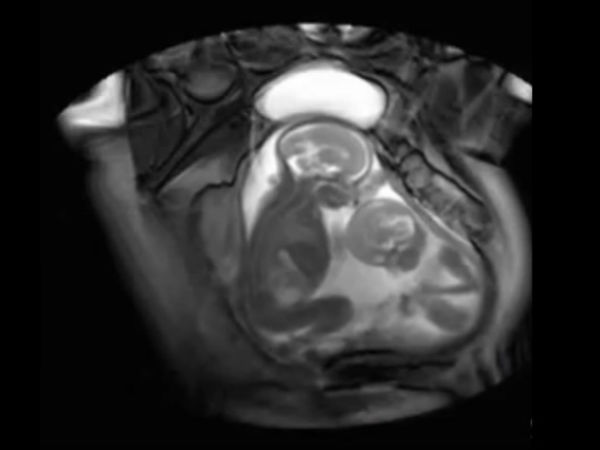

ஒருமுறை உடலுறவில் ஈடுப்பட்டு இரண்டு முறை கருத்தரித்த பெண்!

ஒருமுறை கருவுற்று இரட்டையர் ஈன்றேடுப்பது இயல்பு. ஆனால், அரிய சம்பவமாக ஒரு பெண் ஒருமுறை உடலுறவில் ஈடுப்பட்டு இரண்டு முறை கருதரித்துள்ளார்.

ஆஸ்திரேலியாவின் பிரிஸ்பேன் பகுதியை சேர்ந்தவர் கேட் ஹில்ஸ். இவர் ஒருமுறை உடலுறவில் ஈடுப்பட்டு இரண்டு முறை கருத்தரித்த சம்பவம் மருத்துவர்களை ஆச்சரியப்படுத்தியுள்ளது.

ஒரே பிரசவத்தில் இரட்டையர்கள் கருத்தரிப்பதை நாம் கண்டிருப்போம். ஆனால், ஒரே ஒரு முறை உடலுறவில் ஈடுபட்டு இரண்டு முறை கருத்தரித்த சம்பவம் மக்களையும் ஆச்சரியத்தில் மூழ்க வைத்துள்ளது.

கேட் ஹில்ஸ் பத்து நாட்களில் இரண்டு முறை கருத்தரித்துள்ளார்.இதை மருத்துவர்கள் மருத்துவ முறையில் சூப்பர்ஃபெட்டேஷன் (Superfetation) என குறிப்பிடுகிறார்கள். இது மிகவும் அரிதாக நடக்கும் சம்பவமாகும்.

இந்த அதிசயம் கேட் ஹில்ஸ்க்கு பல்பையுரு கருப்பை நோய்க்குறி (polycystic ovarian syndrome) எனும் கோளாறின் போது ஹார்மோன் சிகிச்சை மேற்கொண்ட பிறகு நடந்துள்ளது.

கருத்தரித்த பத்தாவது நாளில் மீண்டும் கரு முட்டை கேட் ஹில்ஸ்-க்கு வெளியாகியுள்ளது. ஆக்டிவாக இருந்த இவரது கணவரின் விந்து, மீண்டும் புதிய முட்டையோடு இணைந்து இரண்டாம் முறை இவர் கருத்தரித்துள்ளார்.

பொதுவாக கருத்தரித்த பிறகு பெண்களுக்கு கரு முட்டை வெளிவராது. ஆனால் கேட் ஹில்ஸ்க்கு கருமுட்டை மீண்டும் உருவானதால் தான் இவருக்கு சூப்பர்ஃபெட்டேஷன் எனும் இந்த அரிய நிகழ்வு ஏற்பட்டுள்ளது.

ஒரே நாளில் கேட் ஹில்ஸ்க்கு குழந்தைகள் இருவரும் பிறந்தாலும். அவர்கள் இரட்டையர்கள் அல்ல. இருவரும் ஒரே மாதிரி உருவ தோற்றமும் கொண்டிருக்கவில்லை. இருவரும் எடை, வடிவம், கர்ப்பக்காலமும் வேறுபட்டு தான் இருந்தது.

இதுவரை இந்த சூப்பர்ஃபெட்டேஷன் எனும் அரிய வகை சம்பவம் உலகில் பத்து பேருக்கு தான் நடந்துள்ளது என்பது குறிப்பிடத்தக்கது